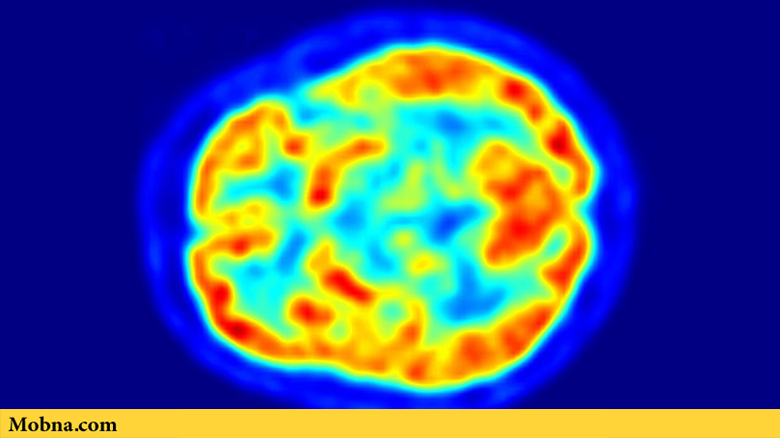

یکی از ابزارهای دقیق که در حال حاضر برای تشخیص بیماری آلزایمر مورد استفاده قرار میگیرد نوعی اسکن تصویری مغز است که با نام «۱۸-اف-فلورودئوکسیگلوکز پیایتی اسکن» یا به صورت اختصاری FDG-PET شناخته میشود. این اسکن به صورت سنتی برای شناسایی انواع مختلف سرطان مورد استفاده قرار میگیرد. ولی در سالهای اخیر پزشکان از آن برای شناسایی آلزایمر و چندین بیماری دیگر مرتبط با زوال عقل هم استفاده کردهاند.

این تحقیق جدید الگوریتم مبتنی بر فناوری یادگیری ماشینی را روی بیش از ۲۱۰۰ تصویر مغزی به دست آمده از اسکن FDG-PET مورد استفاده قرار داد. در حالی که پزشکان انسانی با دقت فراوان تصاویر این اسکنر را ارزیابی میکند، ولی «جائه هو سون» یکی از مدیران این گروه تحقیقاتی توضیح داد که فناوری جدید یادگیری عمیق این امکان را فراهم میآورد تا بتوان الگوهای بیشتری را در این تصاویر شناسایی کرد و از دادههای تصویری، اطلاعات بهتری به دست آورد.

او در این خصوص گفت: «تفاوتهای موجود میان الگوهای جذب گلوکز در مغز انسان بسیار کوچک و نامحسوس است. مردم برای جستوجو و کشف معیارهای خاصی از بیماری بسیار فعال هستند. ولی تغییرات متابولیکی باعث ایجاد الگوهای بسیار ظریفی شده است که انسان به تنهایی و بدون کمک گرفتن از فناوری نمیتواند آنها را شناسایی کند».